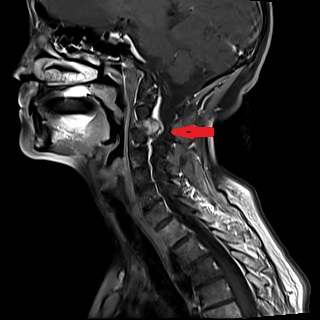

据悉,患者赵婆婆(化名)今年已70岁,日前因反复头晕且有加重趋势前来医院治疗,行头部和颈部核磁检查发现颈2-3右侧椎间孔区占位病变,考虑肿瘤性病变。神经外科医疗团队迅速研究治疗方案后,为其进行行了手术治疗,切除了患者的肿瘤。

术前后术后的核磁对比